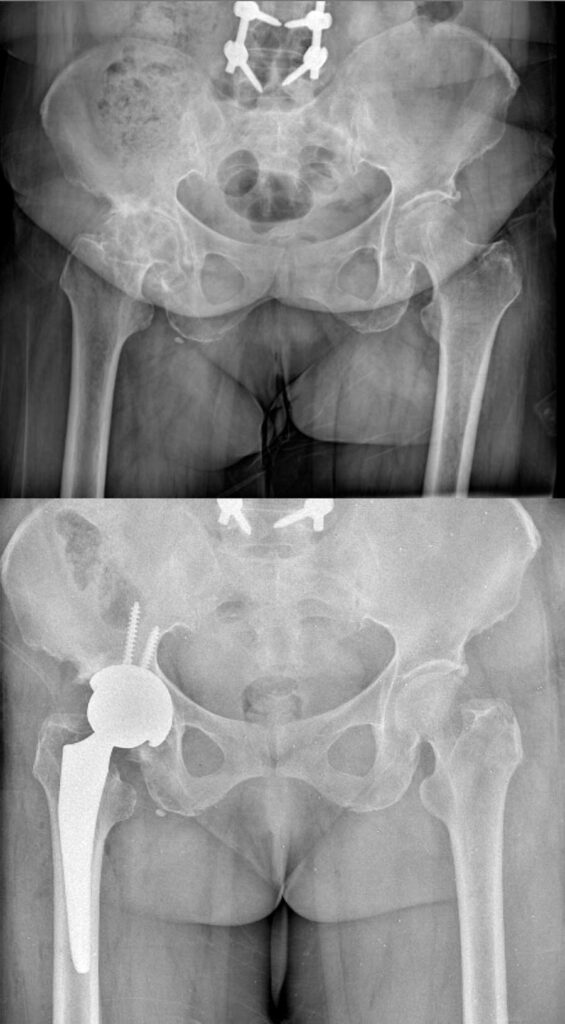

عکس تعویض مفصل لگن

برای آشنایی با تصاویر واقعی رادیوگرافی لگن قبل و بعد از جراحی، عکس تعویض مفصل لگن چند بیمار در زیر وجود دارد. با کلیک بر روی هر کدام از آنها تصویر بزرگتر و کامل را خواهید دید.